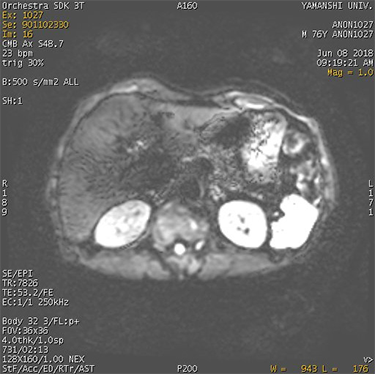

| Wormholes Signal voids in a DWI or EPI image | ![]() | Larger shifts in K-space data due to motion within the diffusion lobe |